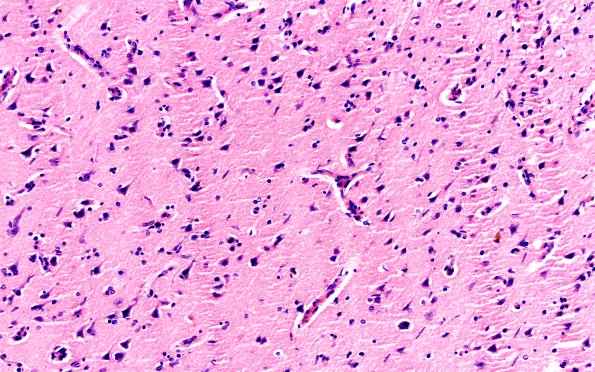

Washington University Experience | INFECTION | Bacteria | Syphilis | 2A7 Syphilis, secondary (Case 2) H&E 15

2A7,8 The vessels show little inflammation in this area; however, there is significant microglial and rod cell formation (arrowheads, 2A8). There is relatively little neuronal loss in this image, not the windswept cortex of general paresis (H&E)